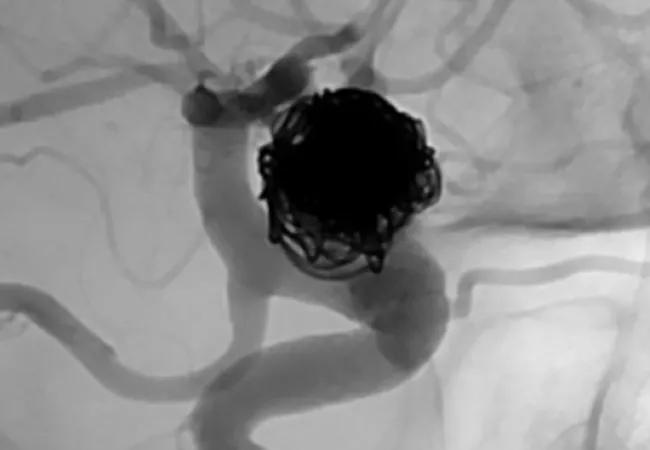

In late 2018, the FDA announced premarket approval (PMA) of the Woven EndoBridge (WEB) Aneurysm Embolization System from MicroVention, Inc. This was the first U.S. PMA of an intrasaccular flow disruptor for aneurysm embolization. The device has been used in Europe since 2010.

The WEB System consists of a permanent nickel/titanium self-expanding mesh ball implant along with a delivery wire and controller. The implant comes in two different shapes and various sizes to match to the aneurysm size. It is inserted in the groin and delivered by endovascular route to the intracranial aneurysm sac, where it deploys and fills the aneurysm. The mesh provides tension so the device remains in place, disrupting blood flow to the aneurysm and thereby promoting thrombosis.

The new device is indicated for endovascular treatment of adults with saccular wide-neck bifurcation intracranial aneurysms with dome diameters of 3 to 10 mm and either neck size ≥ 4 mm or a dome-to-neck ratio between 1 and 2.